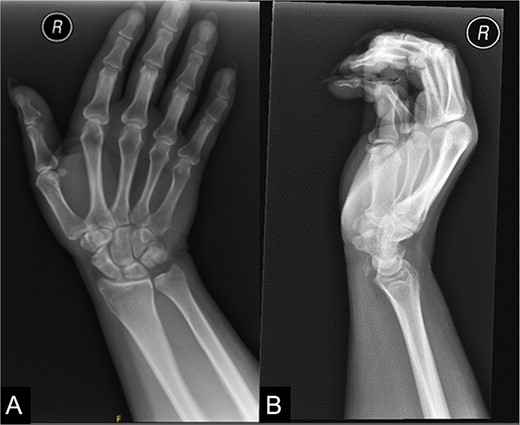

The patient was referred for hand therapy sessions and was prescribed non-steroidal anti-inflammatories to alleviate the pain. She was regularly being followed up in the clinic, where her symptoms had drastically improved after 4 months. A repeat X-ray of her right wrist showed that the previous calcific focus at the flexor carpi radialis tendon region had resolved following conservative management (Fig. 2).

A repeat X-ray of the right wrist indicating that the previous calcific focus at the flexor carpi radialis tendon region had resolved.